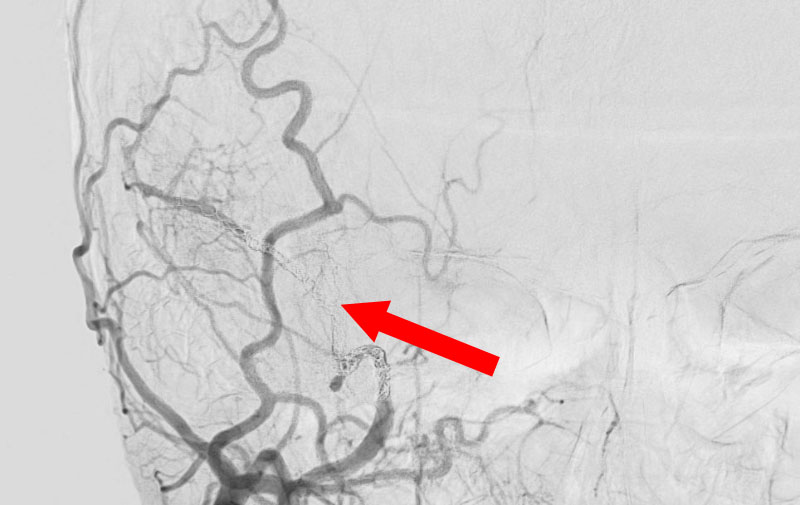

1598

'25年11月26日

右円蓋部髄膜腫

40代

大阪府の病院

治療

後